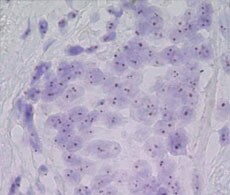

CISH detection of non-amplified HER2 gene status (A) and amplified HER2 gene status (B) in different breast cancer tissue samples at 40X magnification.